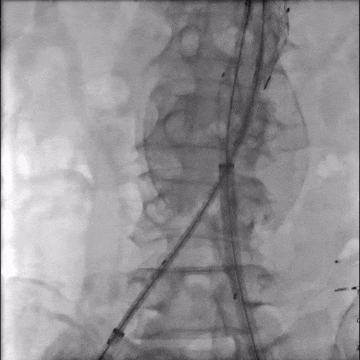

手术采用腹主分支支架,主体释放后行交叉腿髂支延伸。

造影示肾下腹主动脉瘤

选用28-14-140mm主动脉覆膜支架

释放短腿(交叉腿)

导丝超选右髂支

右侧延续16-18-140mm髂支

左侧延续16-18-140mm髂支

术中释放右侧髂支后,患者突发腹痛、心率增快、血压下降,造影怀疑右髂动脉破裂,紧急加放髂支并弹簧圈栓塞。